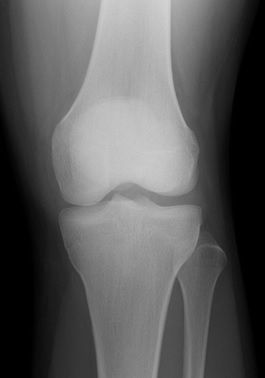

レントゲン所見

| 手術前 | 手術後 |

| 骨傷・関節変形なし | 異常なし |